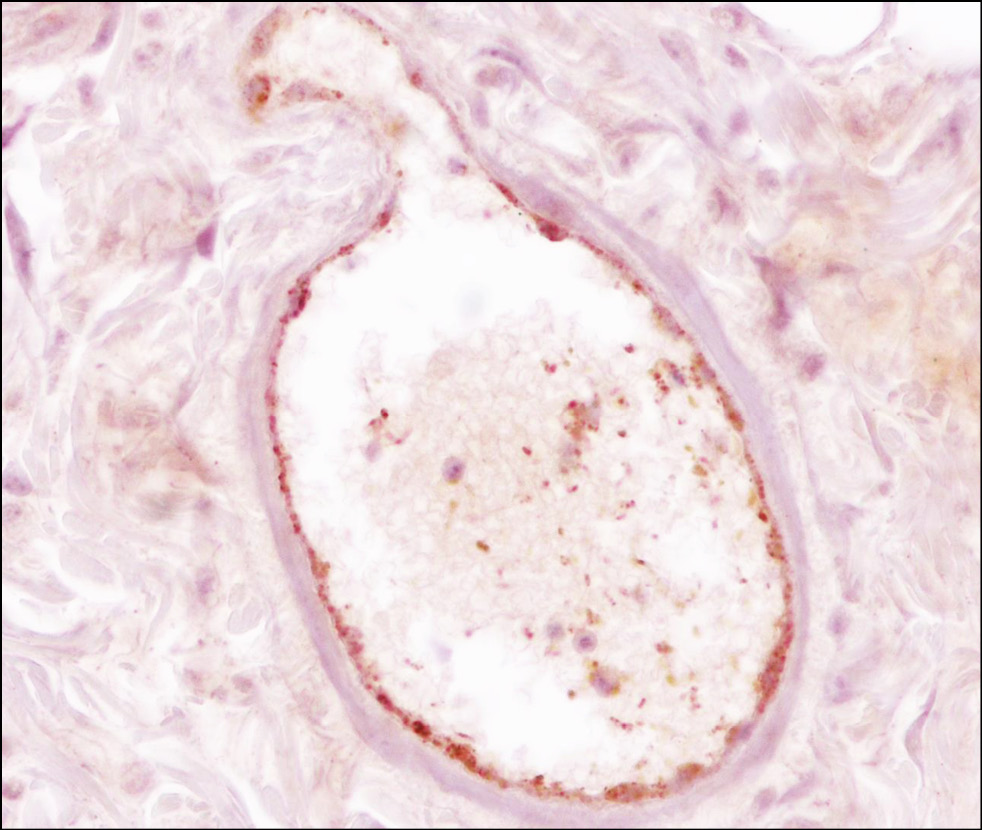

When examining intact skin specimens, only three blood vessels were found in the hypodermis: two large ones (Scp = 604.16 ± 0.61 μm2) and a very large one (Scp = 2578 μm2; Fig. 1).

Fig. 1. Intact skin of the rat thigh. A large blood vessel in the dermis. Immunohistochemical staining with anti–von Willebrand factor antibodies; objective ×40, eyepiece ×10.